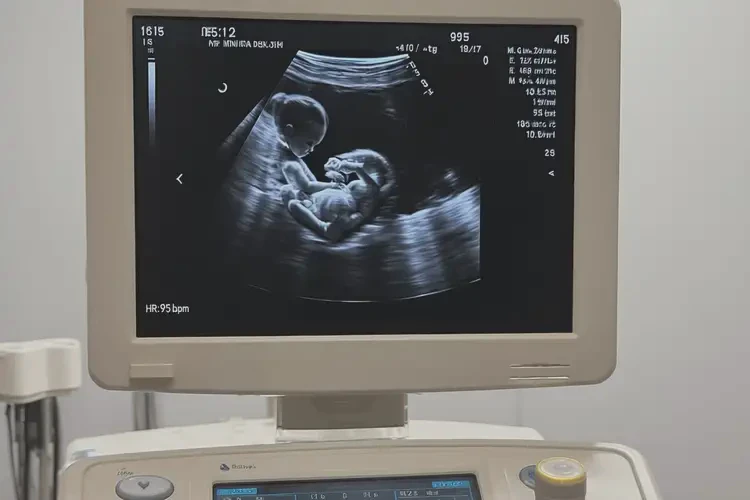

胎心95次/分钟

孕16周时,胎心正常范围通常在140-170次/分钟。胎心95次/分钟明显低于正常值,可能提示胎儿存在某些问题,需要进一步检查和评估。